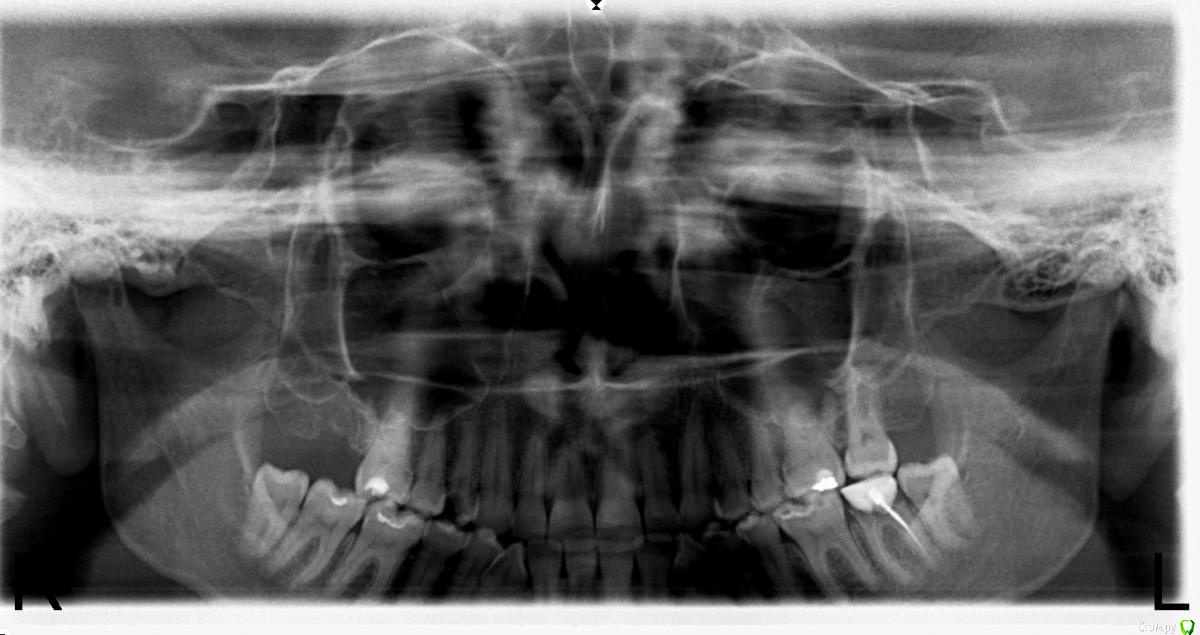

svetok8989 Опубликовано 9 января, 2015 Поделиться Опубликовано 9 января, 2015 Здравствуйте! У меня сильно болит челюсть с левой стороны да и с правой тоже, но с левой сильнее, как будто тянет к уху книзу. сделала рентген , никто не расшифровывает какие зубы могут быть проблемными, верхний 7 зуб справа удалили 2 месяца назад. подскажите пожалуйста, делала кт внчс всё нормально .в чём проблема? Ссылка на комментарий

AlexanderGudkov Опубликовано 9 января, 2015 Поделиться Опубликовано 9 января, 2015 Рентгенлаборанту выговор, переделать оптг в другом месте. Ну и слева снизу на 7 зубе снять пломбу и по результатам диагностики перелечить/удалить. Ссылка на комментарий

orthophil Опубликовано 12 января, 2015 Поделиться Опубликовано 12 января, 2015 Уточните пожалуйста жалобы. Какая челюсть болит верхняя или нижняя, характер болей, когда возникают- утро/вечер, в покое /при нагрузке и т.д.Только по снимку сказать трудно. Ссылка на комментарий